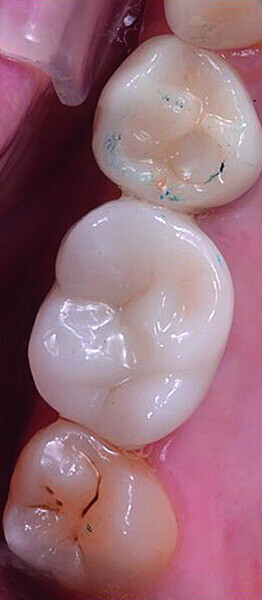

Digital workflow and application of PRF and ozone therapy in oral rehabilitation